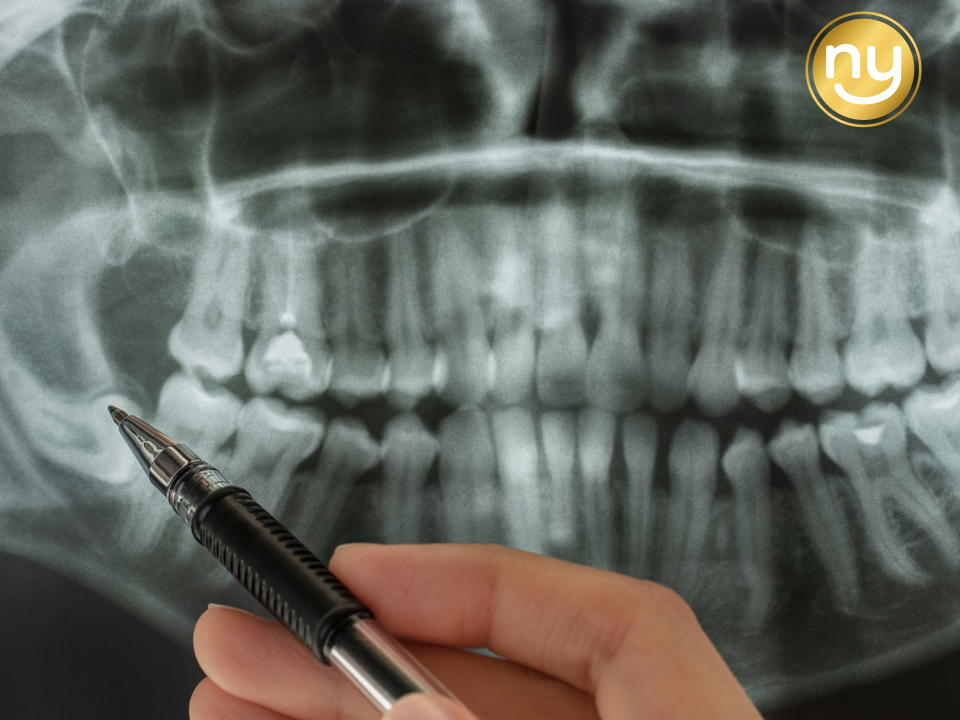

고난도 사랑니의 다양한 유형과 특징

사랑니는 사람마다

자라는 형태가 매우 다양하며,

그중에서도 발치 난도가 높은 경우를

고난도 사랑니라고 합니다.

대표적으로 치아가 옆으로 누워

앞 치아를 밀어내는 ‘수평 매복’,

잇몸 속 깊이 전부 묻혀 있는 ‘완전 매복’,

그리고 신경과 가까운 위치에

자리 잡은 경우가 있습니다.

먼저 사랑니의 위치와 방향을

세밀히 파악한 뒤,

정밀한 CT 장비와 트리오스 구강 스캐너를 활용해

해부학적 구조와 신경관의 위치를

정밀하게 파악하는데요.